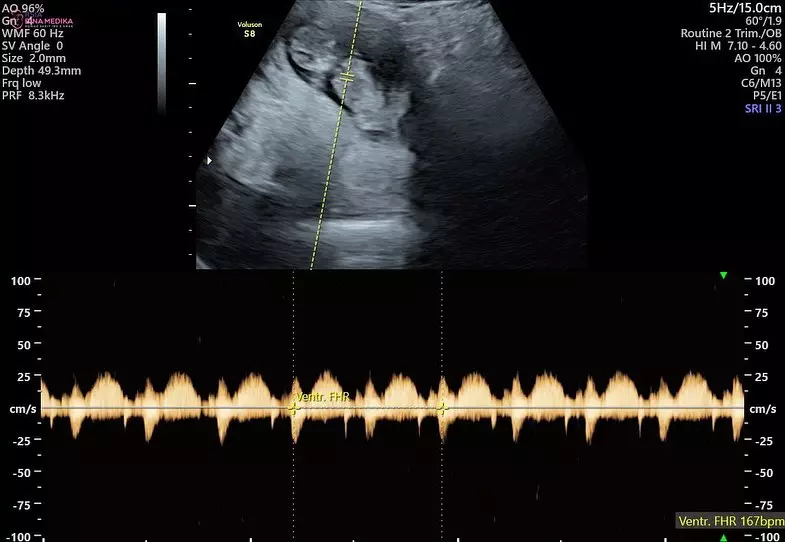

3. Dalam pemeriksaan itu, diketahui usia kandungan Audi Marissa sudah memasuki usia 9 minggu.

foto: Instagram/@audimarissa

4. Tak hanya senang dengan perkembangan janinnya, Audi juga menangis terharu, lantaran ia akhirnya bisa mendengar secara langsung suara detak jantung bayinya.

foto: Instagram/@anthonyxie_